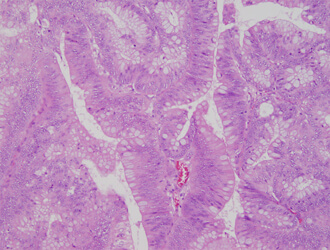

病理検査

病理検査は患者様から採取された手術検体などから、病気の診断や原因を究明することを目的とした検査です。病理検査には組織診断、細胞診断、術中迅速診断が含まれ、病理診断結果はその後の治療方針に直結する検査です。

また、不幸にして院内で亡くなられた方の病理解剖をご遺族の方の同意の下で行い、病気の広がりや死因の究明をする役割も担っています。